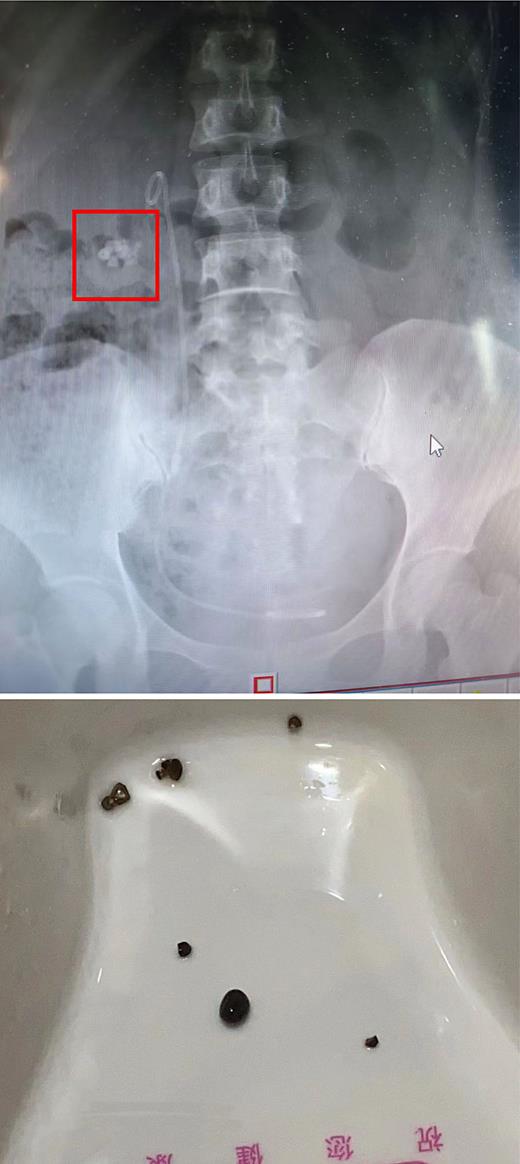

The EPVL system, which was developed in China, has gained increasing recognition and acceptance in recent years. The EPVL technology separates RF from the kidney more easily and is based on simple harmonics. This combination of active adjustments in different postures and external physical vibration can facilitate the clearance of RF in the lower calyceal section of the kidney while shielding the patient’s injured lumbar spine area, which is a significant advantage of EPVL treatment for RF [14]. In a clinical investigation demonstrating that EPVL is a safe, easy, effective, and noninvasive approach for promoting RF excretion following RIRS or ESWL (shown in Fig. 1–4) [17], patients with upper urinary tract stones of approximately 15 mm in size were randomly assigned to a treatment group that received EPVL immediately following ESWL or a control group that underwent only ESWL. At 1, 2, and 4 weeks following ESWL, all patients were reexamined to compare stone size, position, SFR, and complication rate. The SFR was 51.3% (39/76) in the treatment group and 45.4% (35/77) in the control group 1 week after ESWL, while the corresponding values at 4 weeks after ESWL were 90.8% (69/76) and 75.3% (58/77), respectively. In terms of stone removal time, SFR, patient compliance, and acceptability, this study indicated that EVPL was more successful as a supplementary therapy for RIRS than RIRS alone. Zhang et al. [18] found that the best time to perform EPVL was within a 3-day period after RIRS surgery, which yielded the highest SFR and significantly decreased RF complications. Long et al. [4] observed 77 patients who received 1–4 EPVL treatments, of which 71 patients were randomly divided into treatment (n = 34) and control (n = 37) groups. Their results showed that after 3 weeks, the stone clearance rate was 76.5% in the treatment group and 48.6% in the control group. Tao et al. [19] randomly assigned 271 patients to a treatment group (n = 127) or a control group (n = 144). On day 1, the SFR in the treatment group (79.5%) was much greater than that in the control group (64.6%) due to EPVL-assisted RF ejection, while the corresponding values at the end of week 4 were 92.1% and 84.0%, respectively. Li et al. [20] randomly divided 299 obese patients into two groups for a single-center, randomized open-label clinical trial, in which 152 patients received EPVL treatment after ESWL and 147 patients received EPVL treatment after ESWL. EPVL can effectively promote the expulsion of stone fragments. The rate of stone removal on the first day after EPVL was significantly higher in the treatment group than in the control group (66.4% vs. 51.7%, p = 0.009). Stone clearance rates in the treatment and control groups were 2.55% and 1.1% at 63 weeks (p = 0.041), 9.70% and 7.2% at 84 weeks (p = 0.011), and 8.79% and 6.4% at 90 weeks (p = 0.017), respectively. Complications (hematuria, low back pain, and fever) were not significant between the two groups (p > 0.05). Xu et al. [21] studied the efficacy and safety of EPVL in the treatment of distal ureteral calculi through the greater ischial foramina through a randomized controlled clinical trial, proving that EPVL in prone position is a safe and effective method for the treatment of distal ureteral calculi through the greater ischial foramina. All of these studies showed that EPVL can promote spontaneous RF expulsion and significantly shorten the expulsion time after ESWL (shown in Table 1).